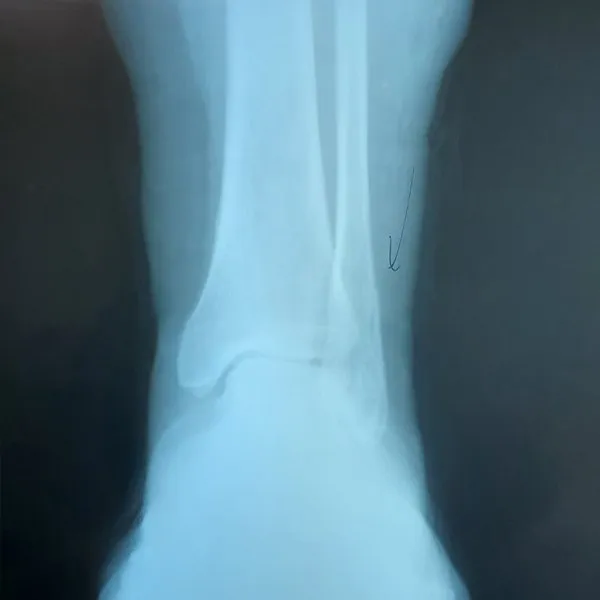

See What's Going on Inside Our Podiatrist's Office

With 32 years of experience, Dr. Daniel Brandwein DPM, PA, FACFAS is your trusted choice for podiatric care in the Pompano Beach, FL area. Take a look at the photos below to see what's happening inside our locally and family owned clinic. To find out how we can help with your foot care needs, please contact us today.